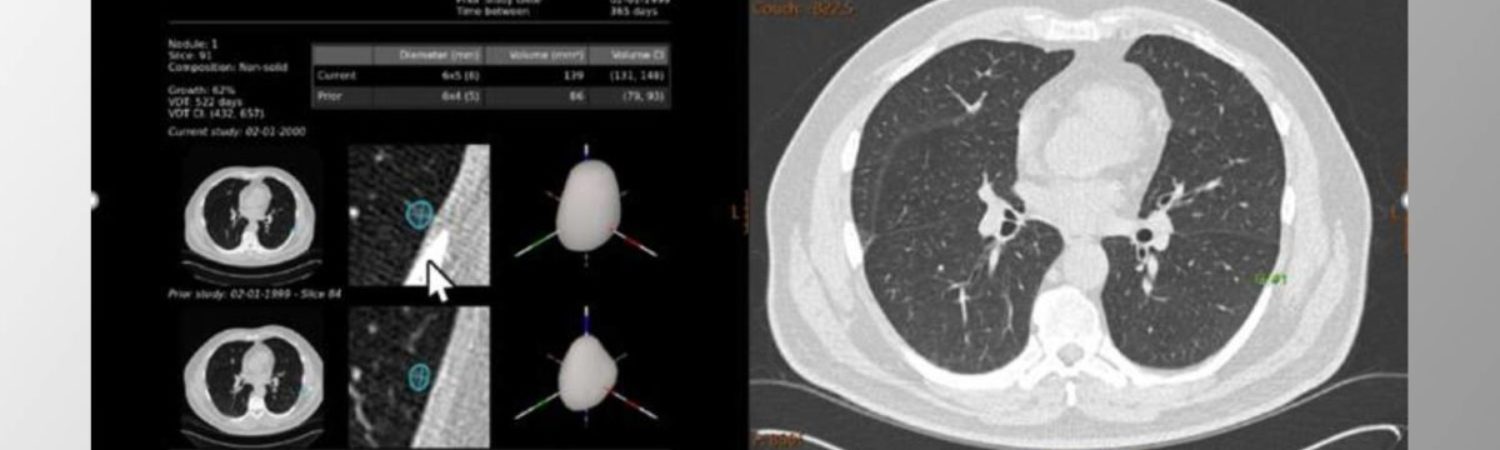

The industry-leading artificial intelligence from Aidence is supporting the TMC lung cancer screening service. Around three-quarters of lung cancer cases are diagnosed at a late stage in the UK and 10-year survival is poor (10%), but 79% is preventable (according to www.cancerresearchuk.org). The AI tool from Aidence, Veye Lung Nodules, helps identify any suspected lung nodules (even nodules as small as 3mm). This AI solution facilitates early lung cancer detection and can thus help save patients’ lives. Approximately 10,000 cases will be analysed by Aidence’s AI solution this year. It can be expected that about 10% of the patients will have a positive finding. (According to Gareth Davies, TMC UK Medical Director).